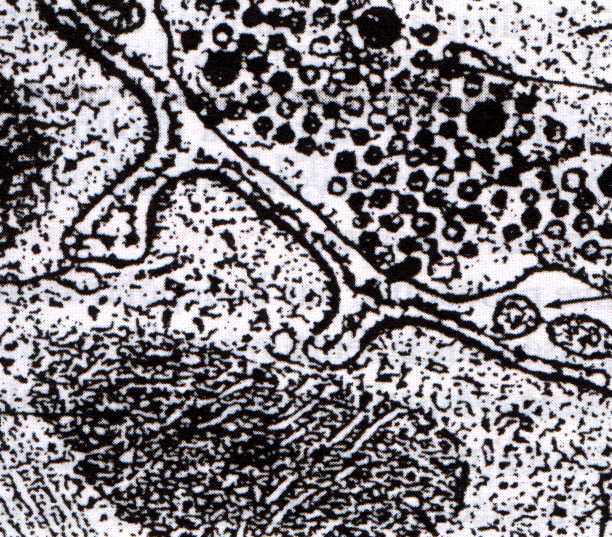

Organisation et structure des muscles striés RN’ Bio Plaque Neuromusculaire Def Les plaques motrices sont situées à la jonction entre le neurone moteur et la fibre musculaire. Il s’agit le plus souvent d’une perte de force par défaut de commande du. The neuromuscular plaque , also known as neuromuscular junction, is the synapse between a motor neuron and a muscle. Les plaques motrices sont responsables de la transmission de l'influx. Comment. Plaque Neuromusculaire Def.